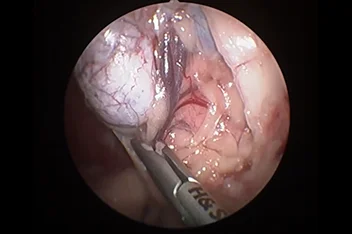

관절경

개,고양이 들은 다양한 관절질환이 존재하고, 복합적으로 존재하는 경우도 빈번합니다.

정확한 진단이 나지 않은 뒤 수술을 하게되면 증상개선이 더디거나 개선이 안될 수 있어, 정확한 진단이 필요합니다.

관절의 경우 X-ray 촬영등으로 진단의 한계가 명확하며, 상위 검사인 CT, MRI 촬영으로도 진단의 한계가 있습니다.

이때 관절경은 내부 구조물들을 직접 시각화 하여 보다 정확한 관절의 상태를 확인하고 진단할 수 있으며, 진단과 치료를 동시에 진행하는 경우도 있습니다. 대표적으로 십자인대단열(CCLR), 골연골염(OCD), 자뼈꿈치돌치유합부전(UAP), 내측관상돌기질환(MCD) 등에 활용될 수있습니다.

관절경 팔꿈치관절(Elbow) 확인

관절경 무릎관절(Stifle) 확인 (반월판 및 십자인대)